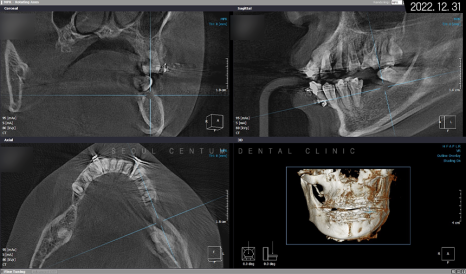

따라서 적정 시기에

CT를 촬영해 치조골 폭과 밀도를

철저하게 분석한 다음 정확한 자리를 선정하고

임플란트 식립을 진행했습니다.